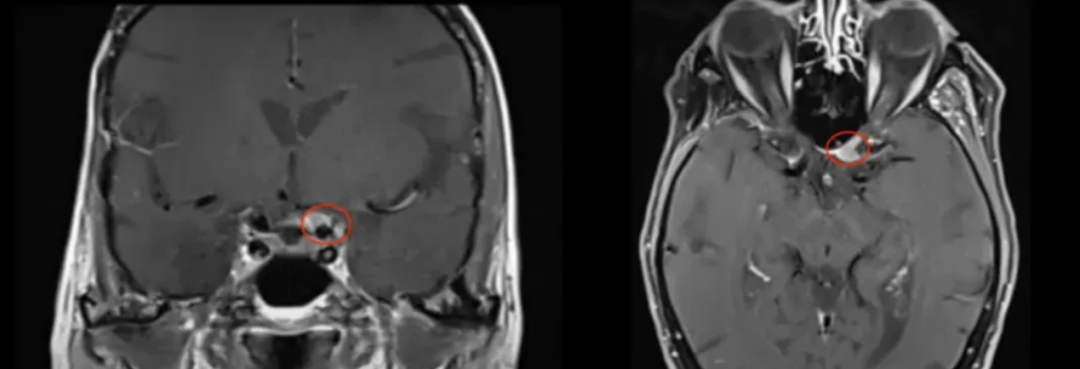

2005年,75岁女性患者行右侧海绵窦脑膜瘤切除术。11年后左眼视力持续下降,检查发现新脑膜瘤压迫视神经管下侧。

86岁高龄患者选择手术治疗。Froelich教授采用内镜辅助右额下入路肿瘤全切术,实现辛普森II级切除。术后视觉功能显著改善,嗅觉功能保留完整,无脑脊液漏发生。

术前及术后MRI对比显示肿瘤完全切除。